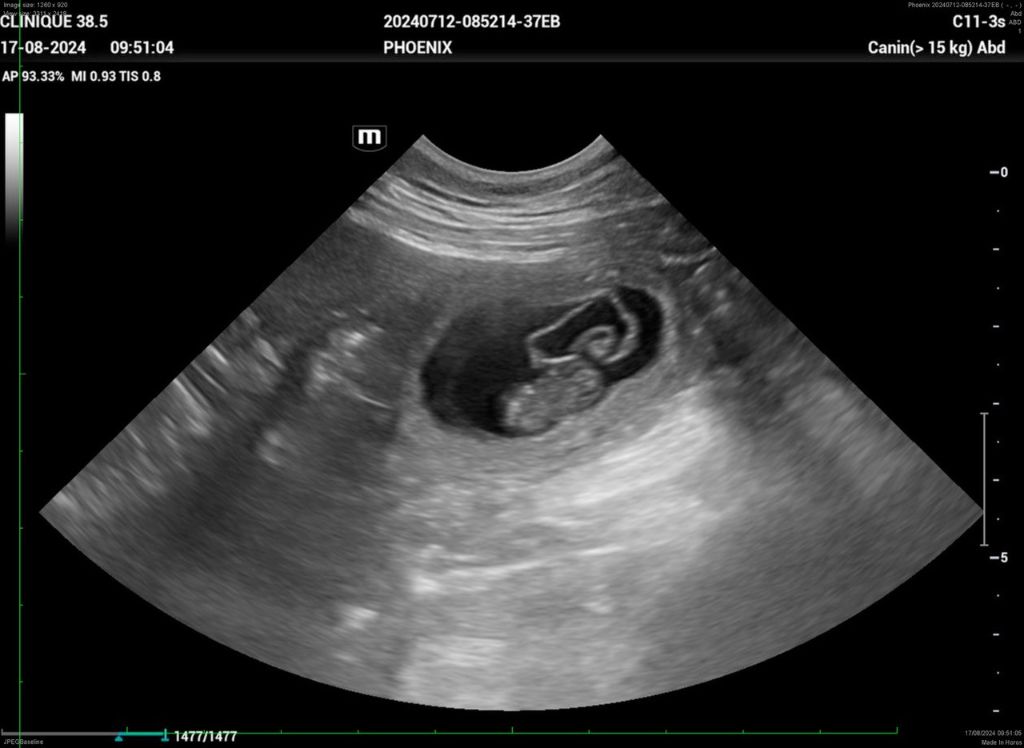

Portée PHOENIX et VITO 2024

Echographie.

Saillie